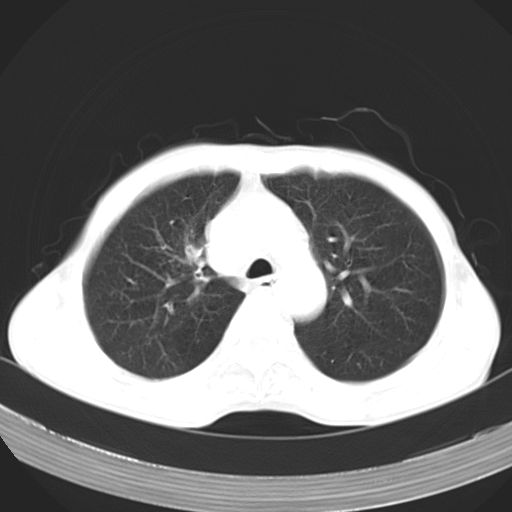

以下是引用苯小孩在2007-5-24 12:47:00的发言:[br]右侧肺门处不均匀密度软组织块影,远端肺组织见斑片模糊影,纵隔内淋巴结明显肿大,边界不清.<纵隔窗第12层面支气管内似见软组织结节>[br]考虑:1、右侧中央性肺癌并阻塞性肺炎并纵隔淋巴结转移可能性大.建议强化或纤支镜进一步检查.[br]2、隆突下淋巴结肿大/食道病变?请做鉴别检查.

以下是引用zhangzhongshou在2007-5-24 12:55:00的发言:[br]1、右肺中叶中心型肺癌并右肺门、隆突下、纵隔淋巴结转移。右肺中叶阻塞性肺炎。

以下是引用jw-830在2007-5-24 15:24:00的发言:[br][br] [br] 考虑右肺中央型肺癌并阻塞性炎症,右肺门及纵隔淋巴结转移。 [br] [br][br]